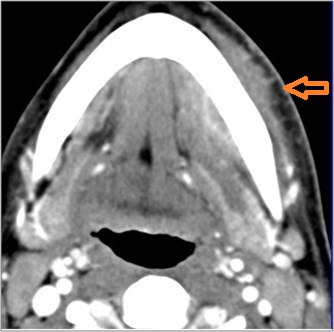

Vascular Findings

There is evidence of thrombus, thrombophlebitis or other occlusive or inflammatory process of the jugular vein or smaller venous tributaries. [Yes/No]

There is evidence of thrombus, inflammation of the common, external or internal carotid artery. [Yes/No]